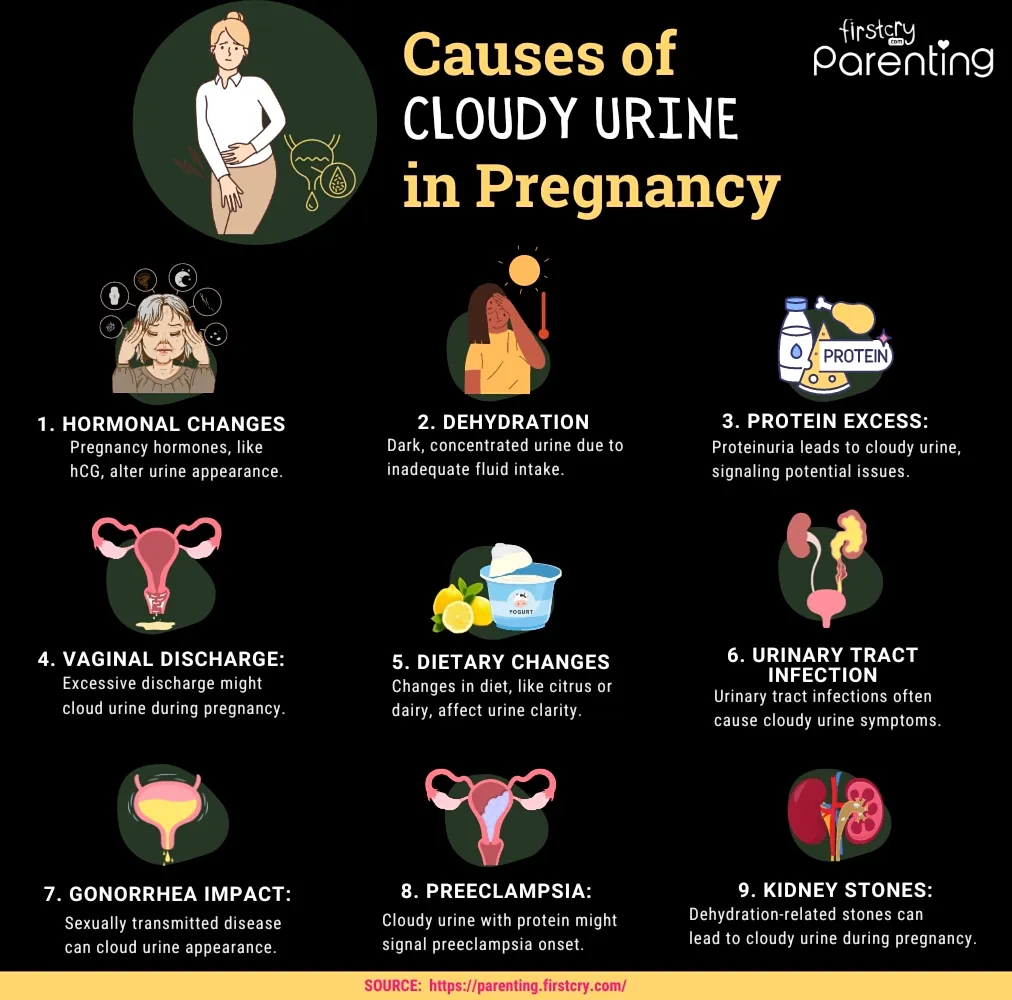

Cloudy Pee during Pregnancy Causes & Home Remedies